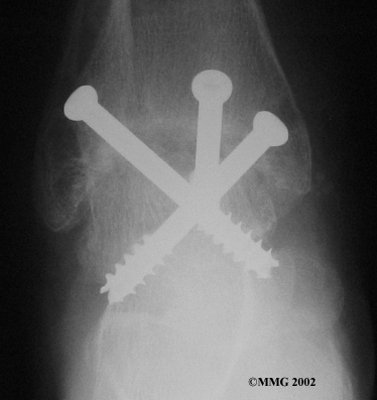

It is important when the surfaces are removed that the angles of the cut surfaces are correct. When the tibia is brought against the talus, the foot should be at a right angle to the lower leg. Once the cuts are made the bones must be held in place while they fuse. This can be done using large metal screws and metal plates if necessary. The screws are usually under the skin and are not removed unless they begin to rub and cause pain.

Inserting the screws

After ankle fusion, the physical therapists at FYZICAL Butler can help you learn to walk smoothly and without a limp. Although time needed for recovery varies among patients, an ankle brace will typically replace your cast after eight to 12 weeks. Your surgeon will take X-rays frequently to see if the bones are fusing together. You will probably need to use crutches during the time you wear the cast. As the fusion grows stronger, you will begin to put more weight on your foot when walking.